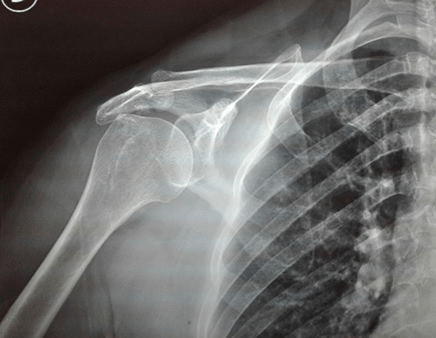

Caso clínico 22/01/2020

Caso clínico 15/01/2020.